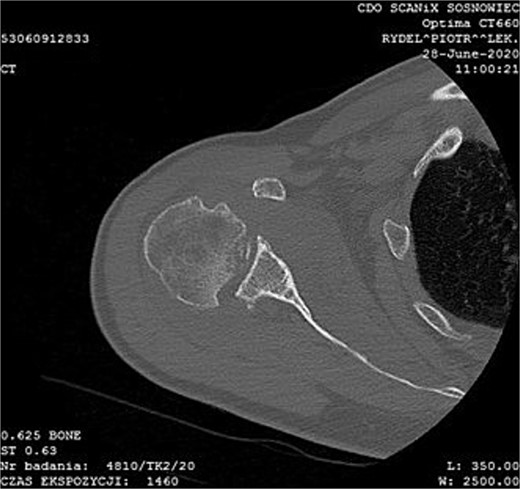

During the outpatient follow-up visit at the Orthopedic Clinic, ~10 weeks after the accident, a physical examination of the patient was conducted, which included shoulder X-ray imaging. The examination revealed severe pain in the right shoulder and a significant limitation in the mobility of the joint (results summarized in Table 1). The above enforced the decision of expanding the imaging diagnostics to look for fractures within the humeral head; hence, computed tomography (CT) and magnetic resonance imaging (MRI) examinations of the right shoulder were carried out. Additional imaging studies revealed a depression fracture of the humeral head covering 2/3 of the articular surface with posterior subluxation of the right shoulder joint. The examination also revealed that the continuity of the tendons of the rotator cuff muscles has been preserved.

MRI images can be found in Figs 3 and 4, and CT images in Fig. 5.